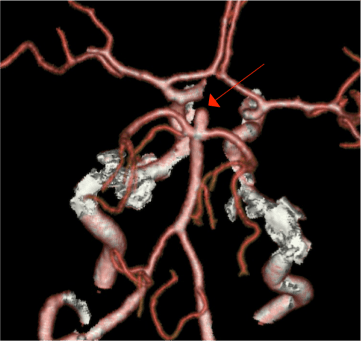

En un metanálisis de 16 estudios que incluyeron 19,559 personas con edades comprendidas entre los 1-97 años sin síntomas neurológicos que se sometieron a una RNM CEREBRAL con o sin contraste con fines de investigación o para exámenes clínicos o comerciales, la prevalencia global de hallazgos incidentales fue del 2,7% (4,3% en los estudios donde los participantes se sometieron al menos a una secuencia de RM de alta resolución frente a 1,7% en los estudios que utilizaron solo secuencias de baja resolución) . Las hiperintensidades de la sustancia blanca, los infartos cerebrales silentes, los microsangrados cerebrales y las variantes anatómicas no se incluyeron en el análisis. Se encontraron los siguientes hallazgos incidentales y prevalencias (%): neoplasia, 0.7 (meningioma, 0.29, adenohipófisis, 0.15, glioma de bajo grado, 0.05, neuroma acústico, 0.03, lipoma, 0.04, epidermoide, 0.03); anormalidades vasculares estructurales, 0.56 (aneurisma, 0.35, malformación cavernosa, 0.16, malformación arteriovenosa 0.05); lesiones inflamatorias, 0.09 (desmielinización definida, 0.06, posible desmielinización, 0.03); quistes, 0,54 (quistes aracnoideos, 0,5; quiste coloide, 0,04), malformación de ChiariI, 0,24; hidrocefalia, 0,10; y colección extraaxial, 0.04 (2)